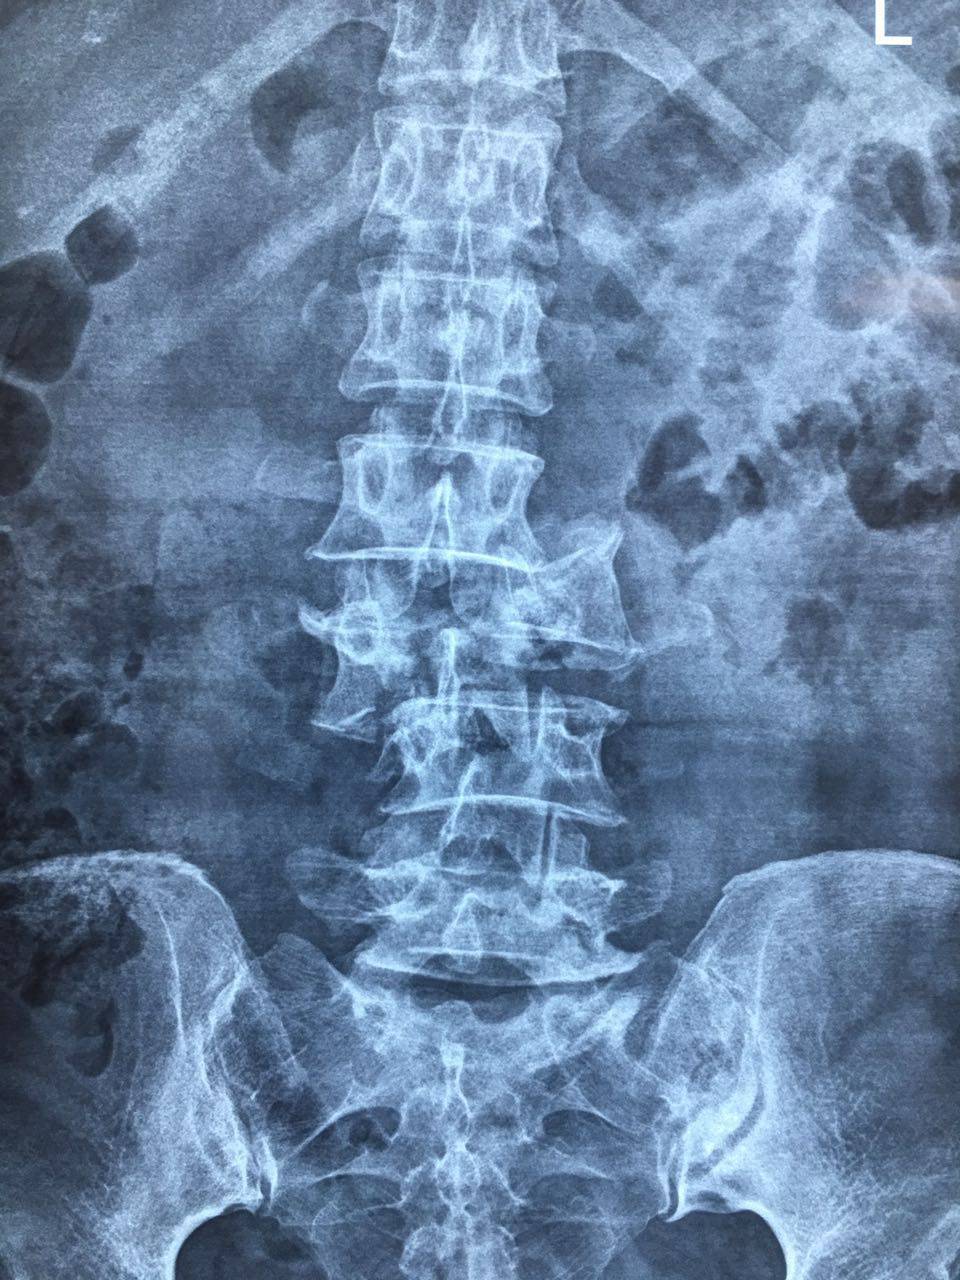

发现患者腰3椎体爆裂性骨折伴脱位,脊髓损伤,腰2,3,4椎体横突骨折

腰1左侧,腰2双侧,腰3-4右侧横突骨折,腰1棘突骨折

腰1椎体爆裂性骨折,腰1 2 3双侧横突骨折